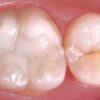

Завданням стоматології «Журавлина» є запобігти у дітей інтенсивний розвиток карієсу як молочних, так і постійних зубів. Причини розвитку карієсу зубів – це патологічний процес, що виявляється після прорізування зубів, при якому відбуваються демінералізація і розм’якшення твердих тканин зуба з подальшим утворенням дефекту у вигляді порожнини. Перші ознаки ураження можуть проявлятися в період прорізування молочних і постійних зубів. Факторами, що сприяють розвитку карієсу в молодшому віці, є порушення структури тканин зуба, що виникли під час ембріогенезу, в антенатальному періоді, під впливом екстрагенітальних захворювань матері.

Сьогодні найбільш точним предиктором виникнення карієсу у індивідуума є значення його індексу інтенсивності карієсу (КПУ / кпу). При наявності каріозних поразок в порожнині рота будь-які профілактичні заходи носять лікувальний характер.

Проведення таких заходів на ранніх стадіях каріозного процесу допоможе запобігти виникненню болю і зменшити витрати на подальше лікування. Всебічний підхід до управління каріозним процесом включає первинну профілактику (навчання гігієні порожнини рота, контроль харчування, зубна паста і ополіскував з фтором), вторинну профілактику (раннє виявлення уражень) і третинну профілактику, яка полягає в мінімальної інтервенції .

Проведення герметизації оклюзійних уражень дентину без утворення каріозної порожнини також ефективне в тимчасовому прикусі. Ідеальний час для чищення – вранці після сніданку і ввечері безпосередньо перед сном. Фторовмісна паста є безпечним засобом незалежно від надходження фториду з інших джерел, якщо використовується згідно рекомендаціям.